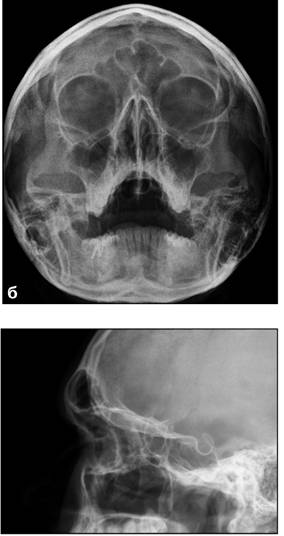

На рентгенограммах глазницы в носоподбородочной,

носолобной и боковой проекциях визуализируются вход в глазницу, ее стенки,

иногда малое и большое крылья клиновидной кости, верхняя глазничная щель (см.

рис. 1).

Рис. 1. Рентгенограммы глазниц в носолобной (а),

носоподбородочной (б) и боковой (в) проекциях